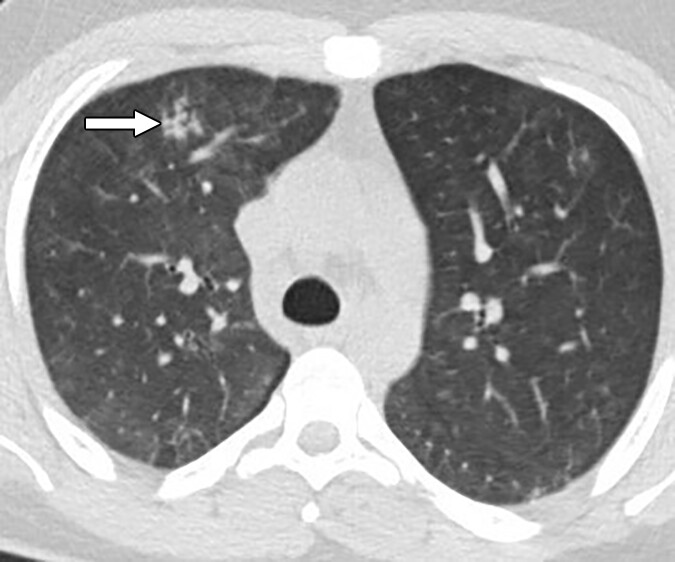

胸部 X 線または CT スキャンでは、肺の損傷や肺の出血を示す兆候が見られる場合があります。